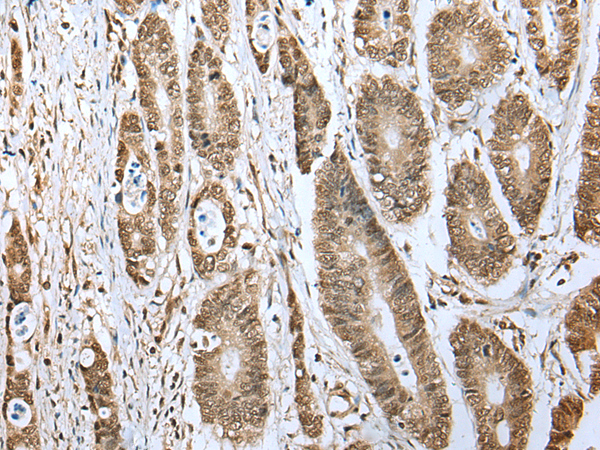

分类: 科研抗体货号: P08827别名: CARB应用: WB,IHC反应种属: Human, Mouse, Rat